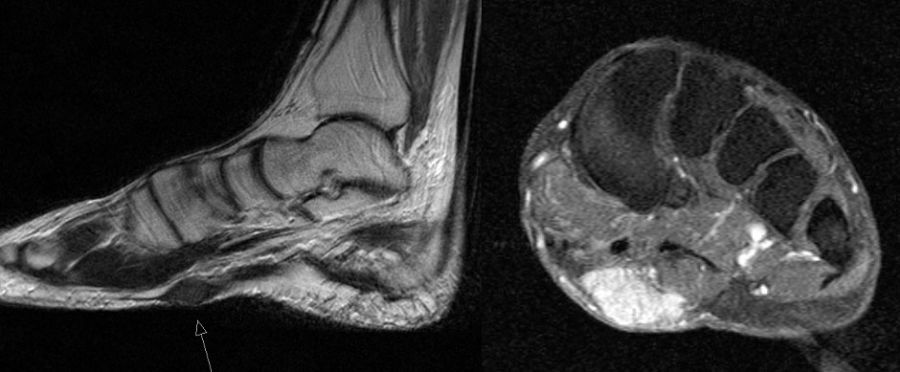

MR-tomographische Darstellung eines unspezifischen weichteiligen Raumforderug im Bereich des dorso-lateralen Rückfußes. Die offene Probebiopsie ergab schließlich die Diagnose eines hochmalignen Synovialsarkoms.

Abbildung 34

10% aller Patienten mit Weichteilsarkomen weisen bei Erst­diagnose bereits Metastasen auf, meist in der Lunge. Drei Viertel der Weichteilsarkome zeigen eine schlechte histo­logische Differenzierung („high-grade“, G3 und G4) und die Letalität beträgt insgesamt über 30%. Trotz des vergleichs­weise seltenen Vorkommens (<1% aller Malignome) gilt diesen Entitäten aufgrund der schlechten Prognose erhöhte Aufmerksamkeit. Das Synovialsarkom ist der häufigste maligne Weichteiltumor im Bereich des Fußes und betrifft hier typischerweise Adoleszente und Erwachsene in der 2. bis zur 5.Lebensdekade (Abb. 34). Zwischen Beginn der Symptome und endgültiger Diagnose­stellung vergehen durchschnittlich 21 Monate. Das Synyovialsarkom zeigt einen unspezifischen klinischen Verlauf mit variabler Wachstumsge- schwindigkeit und kann zahlreiche andere Entitäten imitieren 50. Die Gefahr sowohl pulmonaler/hämatogener als auch lymphogener Metastasen ist hoch.